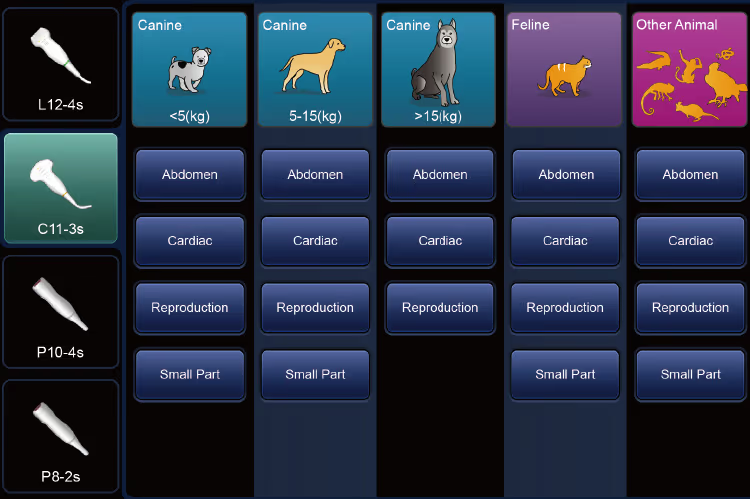

Köpek, kedi, at, sığır, koyun vb. gibi türlere özel profesyonel veteriner görüntüleme ön ayarları sunar, ayrıca özel hayvan türlerini tanımlamayı destekler.

Farklı hayvan türleri, kilo ve vücut boyutuna göre alt gruplara ayrılarak (örneğin küçük köpek, orta köpek, büyük köpek) hassas teşhis imkânı sağlar.Yenilikçi veteriner görüntüleme algoritması ile görüntü kalitesi optimize edilir.

Aynı arayüzde, prob ve muayene modları arasında 1 saniye içinde hızlı geçiş yapılabilir.

Dokunmatik ekranda tek tıklamayla sık kullanılan modlara geçiş sağlanır.

Sade kullanıcı arayüzü tasarımı sayesinde yalnızca ilgili menü seçenekleri gösterilir ve işlemler daha net ilerler.